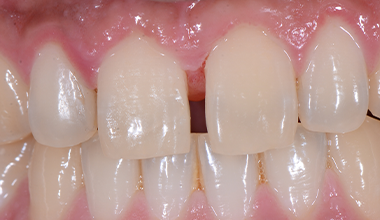

CASE 03

-

치료 전 -

치료 후